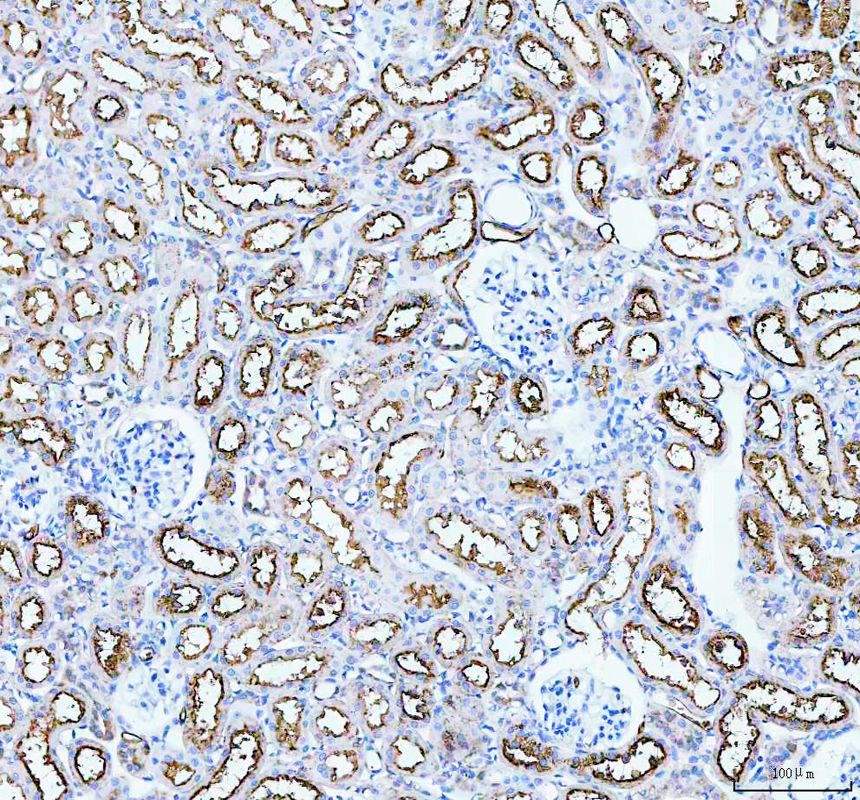

IHC analysis of AQP1 using anti-AQP1 antibody (PB9473).

AQP1 was detected in a paraffin-embedded section of mouse kidney tissue. The tissue section was incubated with rabbit anti-AQP1 Antibody (PB9473) at a dilution of 1:200 and developed using HRP Conjugated Rabbit IgG Super Vision Assay Kit (Catalog # SV0002) with DAB (Catalog # AR1027) as the chromogen.